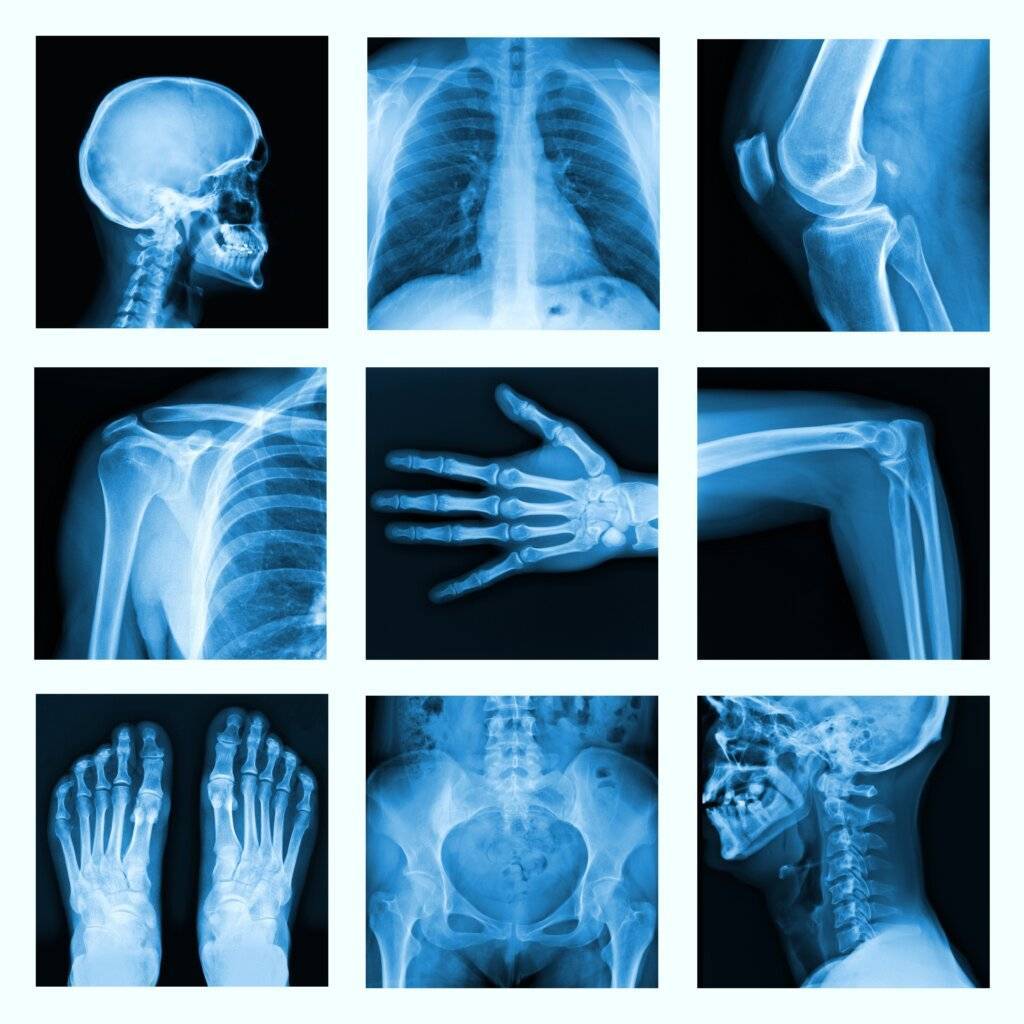

Röntgen, Ultraschall, CT, MRT gehören zu den bildgebenden Verfahren in der Radiologie. Oft wird gefragt: was ist Radiologie? Radiologie ist ein medizinisches Fachgebiet, das moderne bildgebende Verfahren nutzt, um das Innere des Körpers sichtbar zu machen. Dies dient insbesondere zur Diagnostik und ist in der Medizin nicht weg zu denken.

Die Radiologie ist ein medizinisches Fachgebiet, das sich auf die Anwendung bildgebender Verfahren konzentriert, um das Innere des Körpers sichtbar zu machen. Mithilfe von Technologien wie Röntgen, Computertomografie (CT), Magnetresonanztomografie (MRT) und Ultraschall werden detaillierte Bilder von Organen, Geweben und Knochen erzeugt. Diese Bilder sind entscheidend, um Krankheiten zu erkennen, Diagnosen zu stellen und Behandlungspläne zu entwickeln, ohne dass invasive Eingriffe notwendig sind. Radiologische Untersuchungen werden häufig zur Diagnose von Verletzungen, zur Früherkennung von Krebs und anderen Erkrankungen sowie zur Überwachung von Behandlungen genutzt.

Röntgen

Das Röntgen ist eine der ältesten und am weitesten verbreiteten Methoden der Radiologie. Es nutzt Röntgenstrahlen, eine Form elektromagnetischer Wellen, die den Körper durchdringen. Dichte Strukturen wie Knochen absorbieren die Strahlen stärker und erscheinen auf dem Röntgenbild als helle Bereiche, während weniger dichte Gewebe wie Muskeln oder Lungengewebe dunkler erscheinen. Röntgen wird vor allem zur Untersuchung von Knochenbrüchen, Gelenkerkrankungen, Lungeninfektionen und Zahnproblemen verwendet. Es ist eine schnelle und kostengünstige Methode, die jedoch mit einer geringen Strahlenbelastung einhergeht.